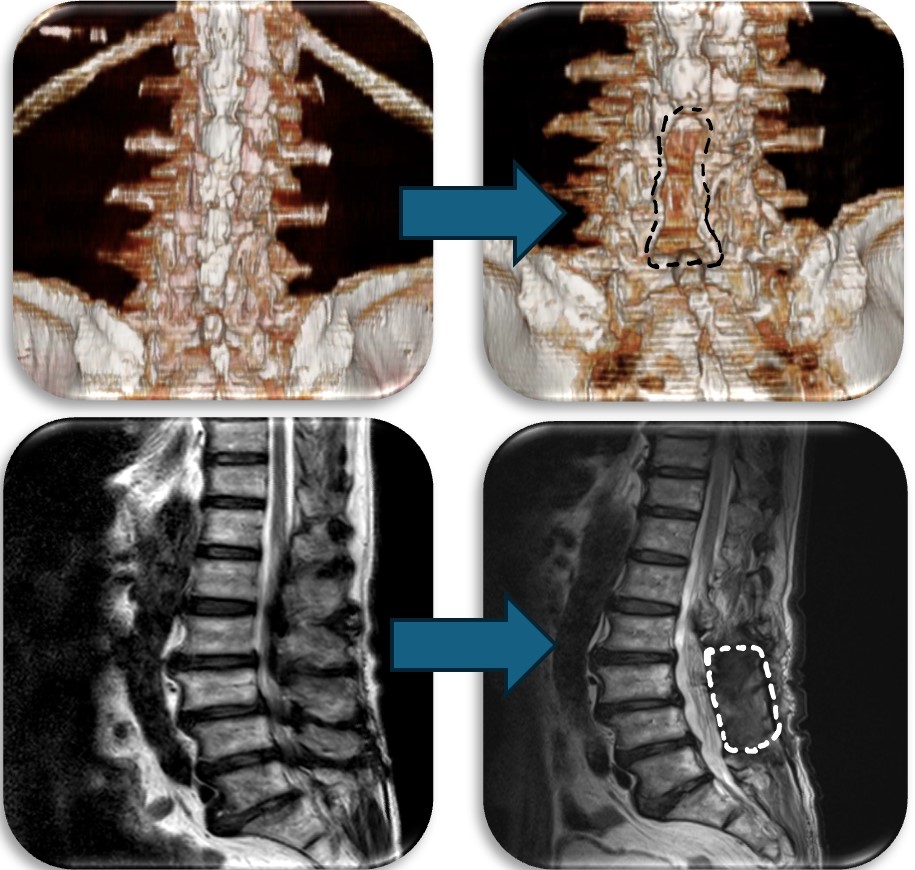

(代表例)

腰部の馬尾神経に発生した神経鞘腫の症例。脊髄腫瘍としては比較的多く割合を占める神経鞘腫は良性腫瘍であり、基本的には全摘出が可能で予後も良好です。この症例も坐骨神経痛と間欠跛行という馬尾障害の症状を呈していましたが、術後は改善し再発も認めておりません。